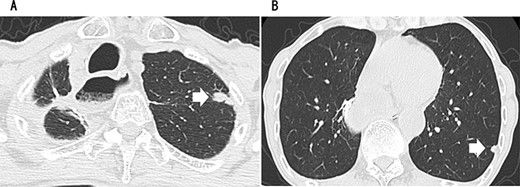

A 79-year-old man underwent right subthoracic esophagectomy and posterior mediastinal reconstruction for esophageal cancer (squamous cell carcinoma, pT3N4M0 Stage IVa) 9 years ago. The patient had previously undergone four cycles of CDDP+5-FU. After esophagectomy, the patient developed ileus three times; it was conservatively managed. During the third hospitalization, chest computed tomography (CT) showed a circular nodule measuring 1.4 cm in the S1 apex of the right upper lobe and a nodule measuring 0.9 cm outside S2 (Fig. 1). No findings were suggestive of esophageal cancer recurrence. 18F-Fluorodeoxyglucose-positron emission tomography revealed FDG uptake increated in the nodule in the right lung S1 with a maximum standardized uptake value of 4.3 and in the nodule in the right lung S2 with a maximum standardized uptake value of 2.7. No significant hilar or mediastinal lymph node swelling or distant metastases were detected. Bronchoscopic biopsy did not reveal any signs of malignancy. Based on the above findings, we suspected multiple lung metastases secondary to esophageal cancer, metachronous primary lung cancer or intrapulmonary metastasis secondary to primary lung cancer. We performed partial resection of the two nodule in the upper lobe of the right lung for diagnosis and treatment. Histopathological examination revealed squamous cell carcinoma (Fig. 2). Immunostaining was performed to determine whether the primary organ was the esophagus or the lung, but no diagnosis was made. On request, no additional chemotherapy was administered. Chest CT after 1 year and 2 months of right lung resection revealed a nodule measuring 1.5 cm at the apex of the left lung and a nodule measuring 0.9 cm below the S9 pleura of the left lung (Fig. 3).

Since no other findings suggestive of distant metastasis were found, partial left lung resection was performed for the two nodules. Both were diagnosed as squamous cell carcinomas (Fig. 4). Furthermore, 5 months after left lung resection, a metastatic liver tumor was found, which was also surgically resected. Finally, 10 years and 4 months after esophagectomy, 3 years after the first lung resection and 1 year after hepatectomy, the patient died due to peritoneal dissemination.

CT revealing a nodule measuring 1.5 cm at the apex of the left lung (A) and a nodule measuring 0.9 cm below the S9 pleura of the left lung (B).